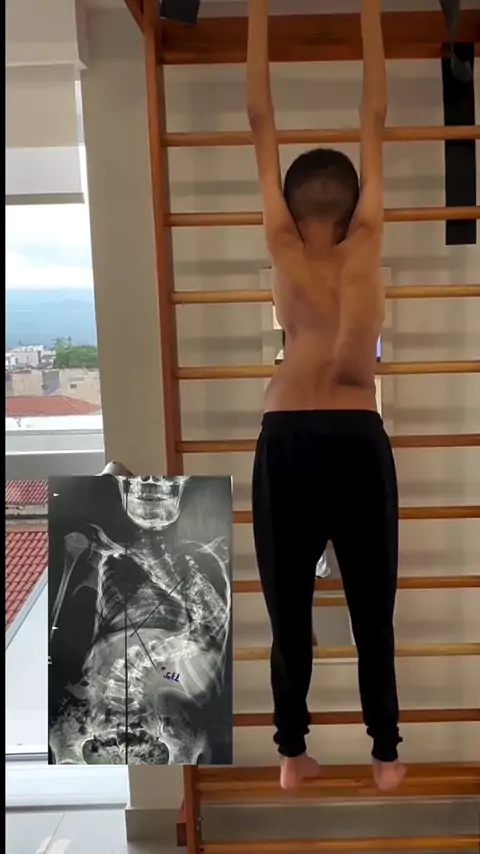

Cuidar da postura, manter o peso ideal e fortalecer o abdômen e as costas são as melhores armas contra a hérnia de disco. Afinal, prevenir sempre dói bem menos do que tratar. #hérniadedisco #coluna #postura